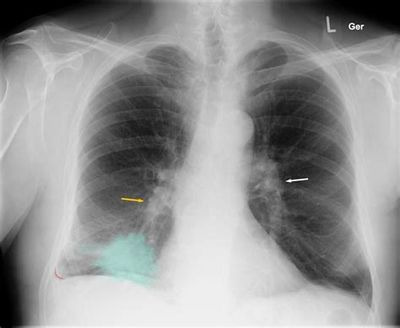

소세포 폐암 진단 방법 🔬

소세포 폐암 말기 진단은 여러 검사를 통해 암의 크기, 위치, 전이 여부를 확인하게 됩니다.

주요 검사 종류

- 흉부 X-ray 촬영